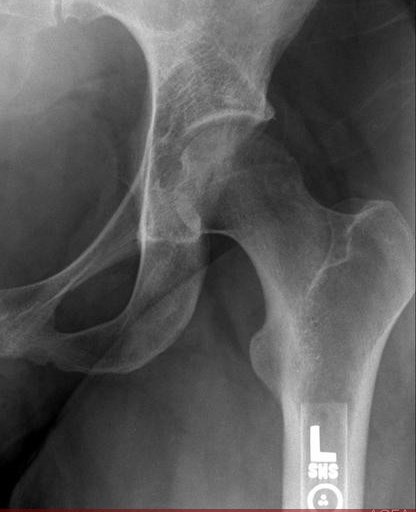

There is a pre-radiologic al phase of 1-2 months following which the osteopenia diffusely involves femoral head and neck. This may be confused with AVN or femoral neck stress fracture. The joint space is always preserved.